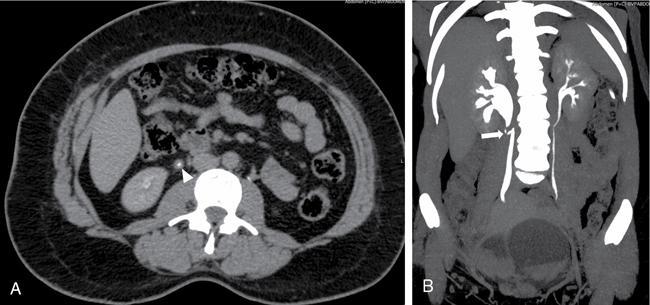

1. A. Intrinsic Causes (Fig. 10.14.4)

Image

Fig. 10.14.4 Benign ureteric stricture: CT Urography study of a 36-year-old female who complained of right lumbar pain. Axial image in excretory phase (A) shows inflammatory thickening of the proximal right ureter (white arrowhead). Coronal MIP image (B) shows inflammatory thickening and kinking of proximal right ureter (white arrow) causing moderate hydronephrosis.